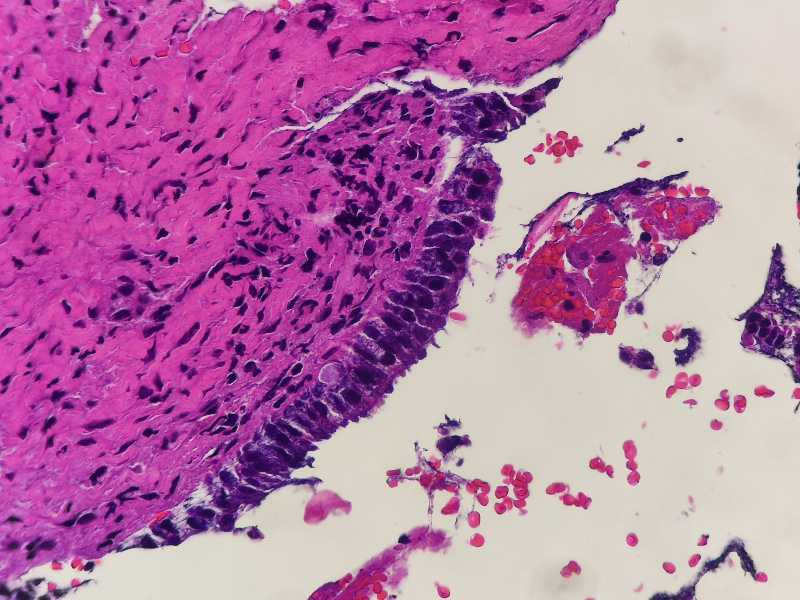

女49岁宫颈糜烂,HPV16和HPV18阳性。宫颈腺体异型原位还是浸润?